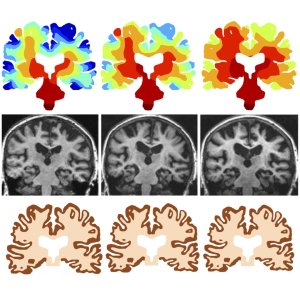

Top row: evolution of the toxic protein through the brain

Middle row: MRI of a patient with Alzheimer’s disease in three successive years

Bottom row: shrinking pattern predicted from the mathematical model

The team ran the mathematical model simulated in full brain geometry obtained from MRI scans but with different initial seeding regions characteristic of each disease. Remarkably, this model reproduces the characteristic evolution of different neurodegenerative diseases, the evolution of the total toxic protein load, as well as the typical atrophy patterns associated with tissue removal. This initial model provides a better qualitative understanding of the mechanisms at work during the evolution of these diseases and opens the door to a new quantitative and physics-based approach to studying the propagation of neurodegenerative diseases and identifying new therapeutic targets.